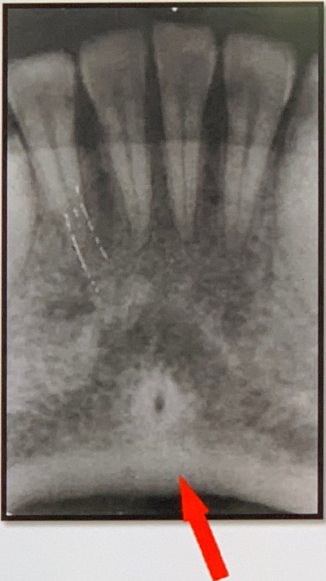

85. What is showing by arrow?

Genial Tubercles (Mental Spine) bony protuberances located on the lingual surface of the mandible slightly above the inferior border and in the midline. serve to attach the genioglossus muscles (at the superior tubercles) and the geniohyoid muscles (at the inferior tubercles) to the mandible. Usually well visualized on mandibular occlusal radiographs as one or more small projections.